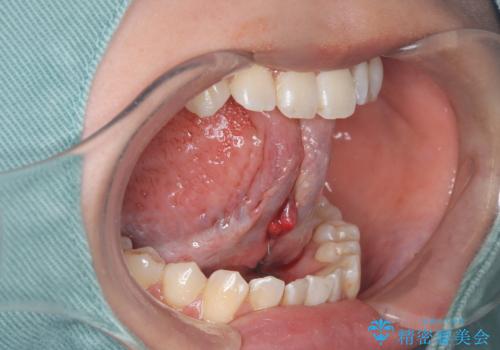

短い舌小帯に舌が引っ張られて舌がハート型になっています。

今まで動いていなかった舌は筋肉が衰えてますので、術後はMFT(舌を動かす訓練)を行うことが大事です。